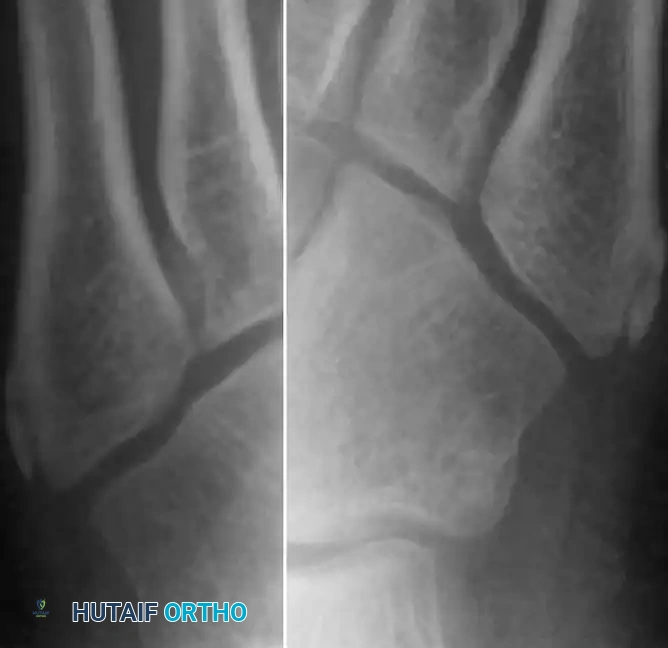

Clinical Pearl: To differentiate MED from Perthes disease, evaluate the bone age. In Perthes disease, the bone age typically lags 1 to 2 years behind the chronological age. In contrast, bone age usually remains normal in multiple epiphyseal dysplasia. Furthermore, radiographs of the ankle in MED often reveal characteristic lateral narrowing or wedging of the distal tibial epiphysis.

Lateral and oblique radiographs demonstrating the smaller, highly sclerotic, and flattened navicular characteristic of Köhler disease.

Diagnostic Pitfall: The appearance of multiple ossification centers in the navicular without an increase in radiographic density should not be confused with Köhler disease. In an asymptomatic foot, this is merely a normal variant of irregular ossification.